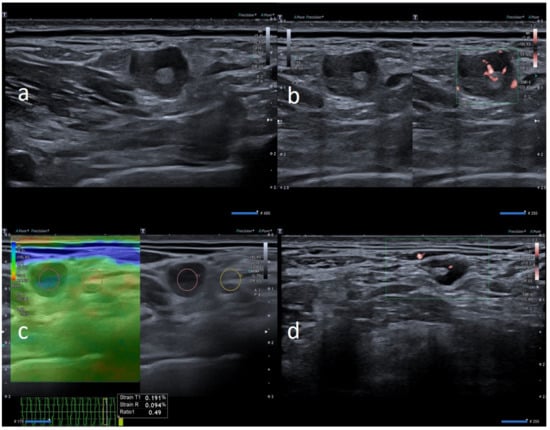

| W | 25 | Pfizer | Axillary ipsilateral to vaccine injection | Three days after first dose of vaccine, axillary swelling and pain present. Also hypomobility ipsilateral arm | None | 6 | Variable: from 0.7 cm to 2.8 cm | Ovular | Prev. no hilum evidence | Prevalent hard pattern | Central and peripheral vascular signals | Normalized to 60 days |